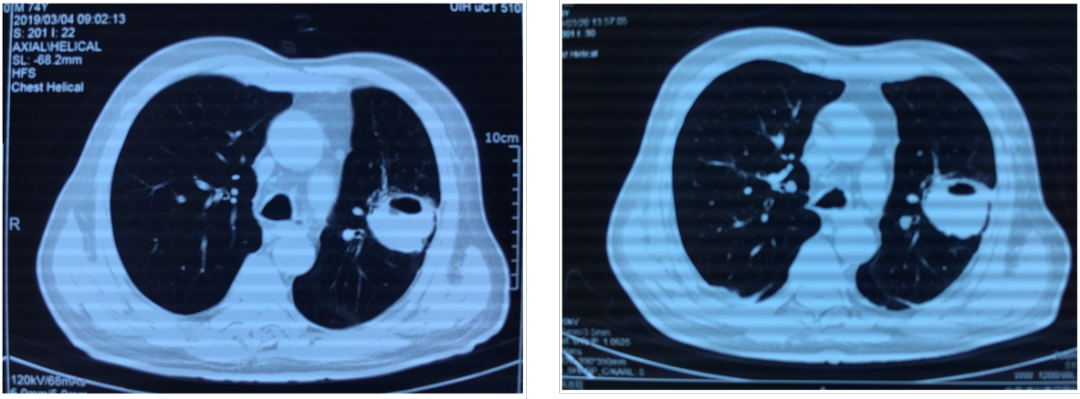

在此期间,抗真菌治疗2周时复查胸部CT:结节空洞体积缩小,壁变薄。但继续抗真菌治疗后,肺部病变较前进展(如下图1、2)

图1 胸部CT进展情况

图2 服用伏立康唑后4周,肺内结节进展